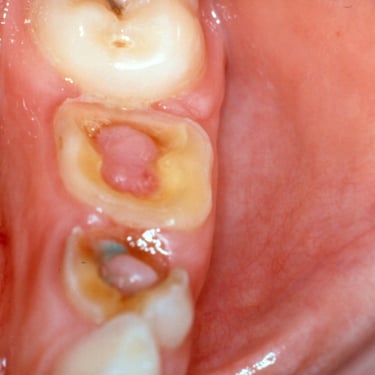

Pulpitis Crónica Hiperplásica

La pulpitis crónica hiperplásica es una inflamación de la pulpa con crecimiento excesivo de tejido pulpar a través de una caries abierta.

Los pacientes notan un tejido rojo que sobresale de la cavidad dental.

El tratamiento incluye la eliminación del tejido afectado y un tratamiento de conducto. Es crucial tratar la caries para evitar infecciones adicionales.